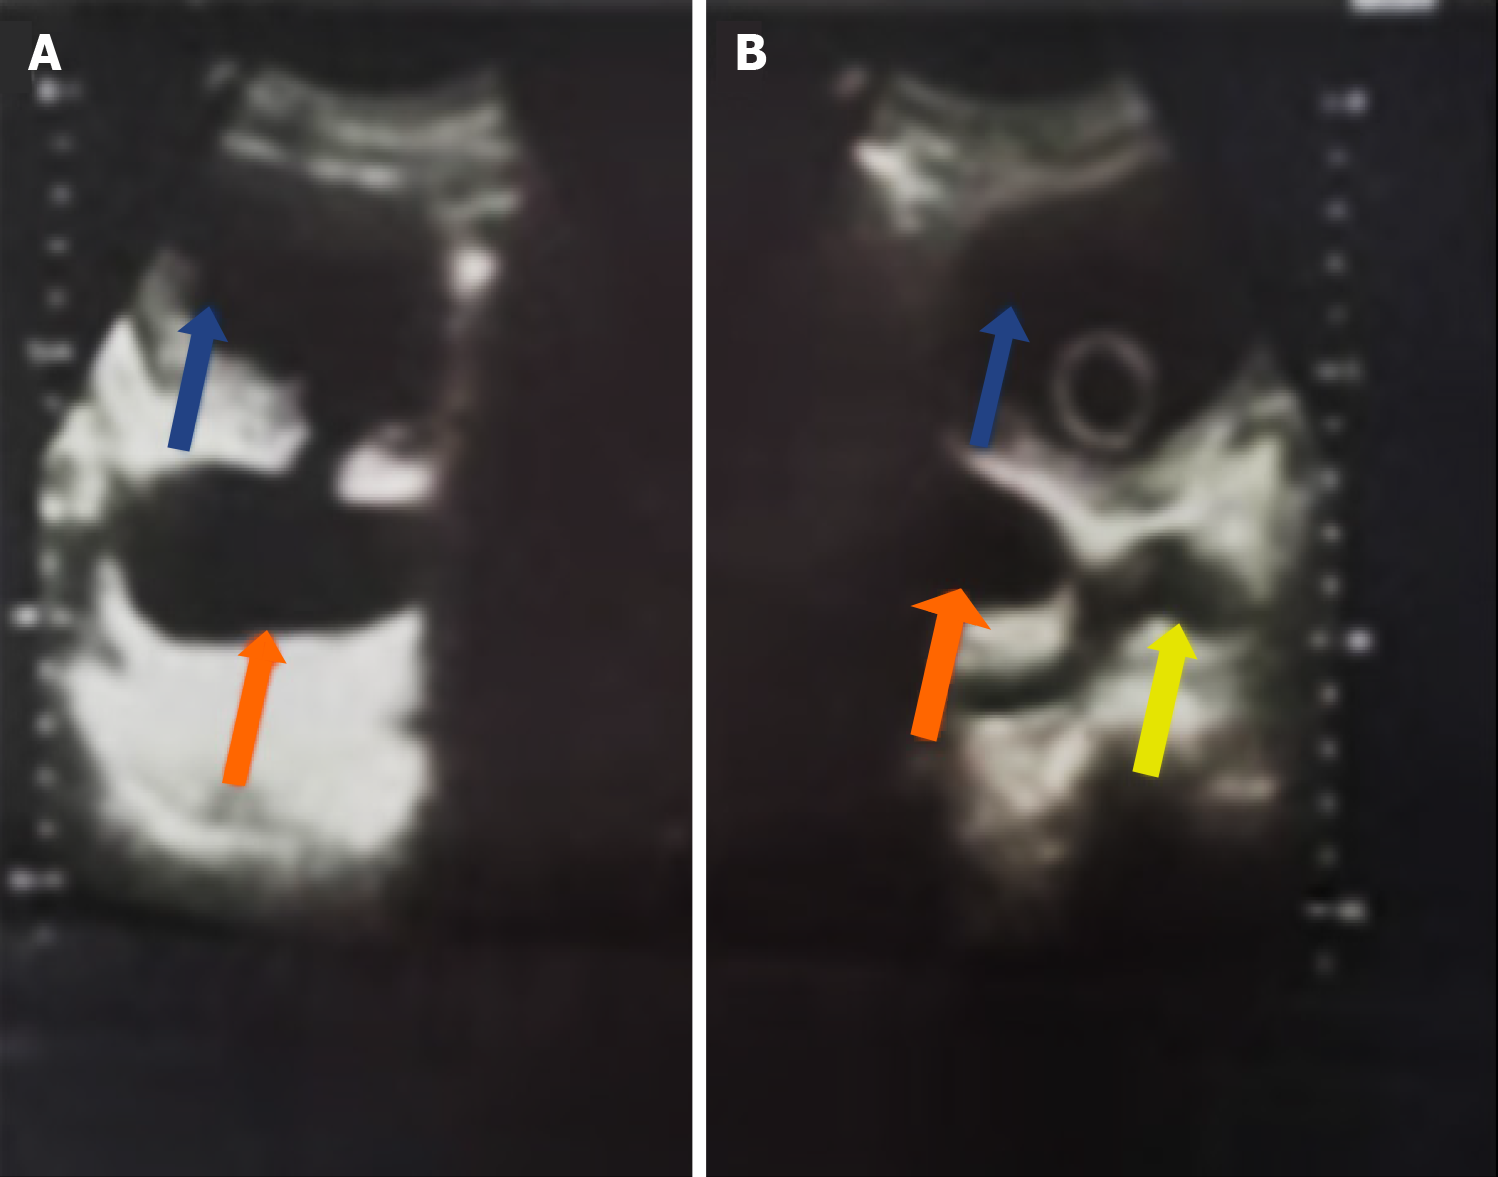

Figure 1 Transabdominal ultrasound scan.

A: Initial presentation of a patient with chronic urinary retention caused by benign prostatic hyperplasia and bladder diverticula (orange arrow), which are indistinguishable from the dilated bladder (blue arrow); B: Repeat ultrasound scan of the same patient after urethral catheterization, showing the right and left-sided bladder diverticula (orange arrows), bladder (blue arrows), and prostate (yellow arrow).